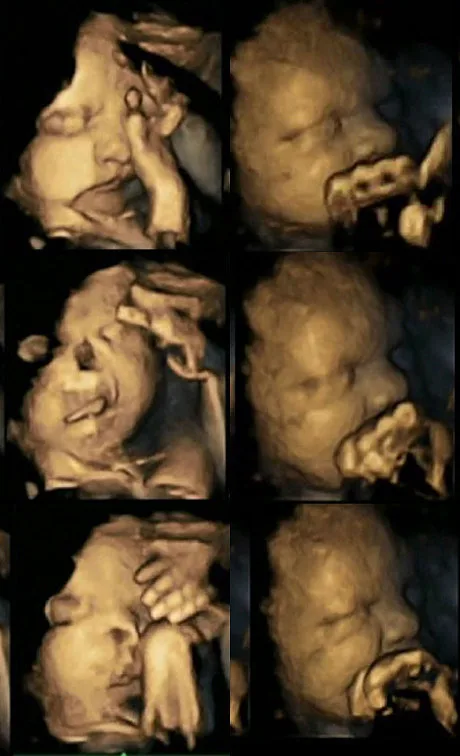

Fetuses of mothers who smoked, it turns out, showed more mouth movements and self-touching than fetuses of non smokers -- and given these types of movements typically decline as babies mature, this suggests that those exposed to cigarettes were neurologically underdeveloped. Check out a side-by-side comparison below of a baby whose mother smoked on the left, non-smoker on the right:

What's eerie is that it almost looks like the babies of smokers are grimacing or cringing ... researchers hope these images will help convince pregnant women to stop smoking, and I hafta say, if these images won't get them to kick the habit, nothing will!

Image via Durham University[